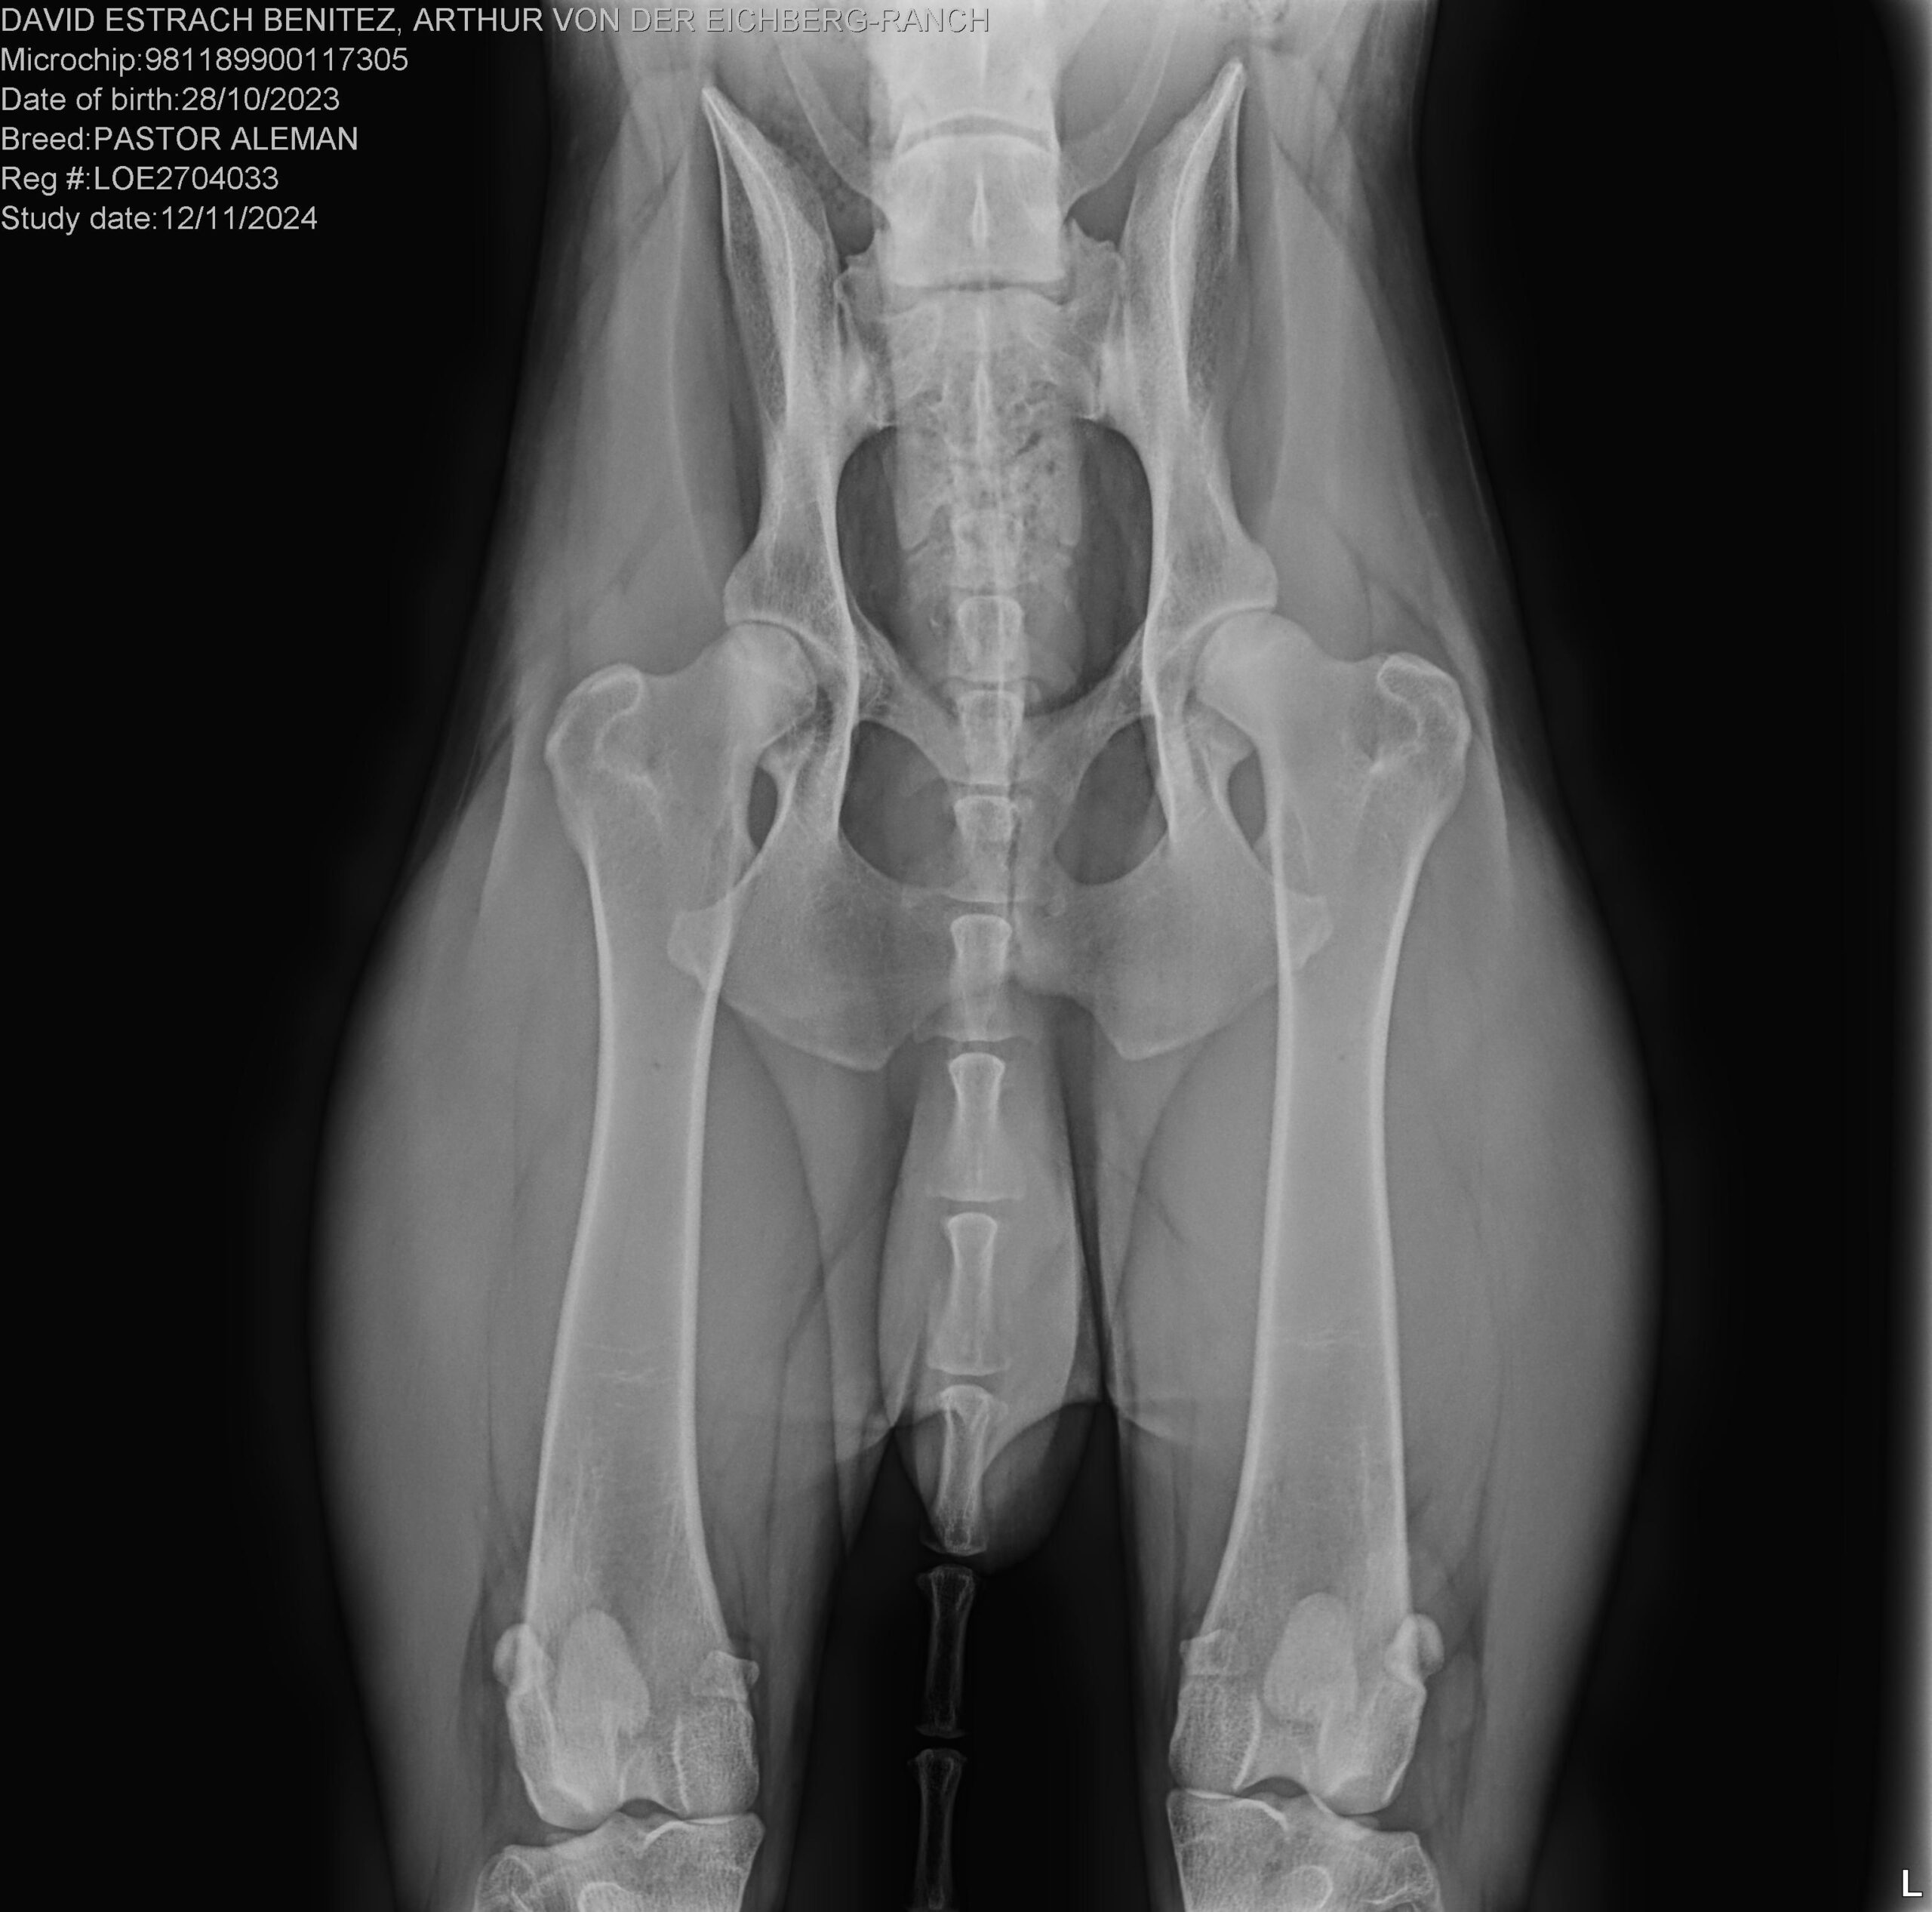

Ya tenemos los resultados de las radiografías oficiales de Arthur von der Eichberg-Ranch, nuestro futuro reproductor de las próximas CAMADAS H y I, programadas para el 2025

CERTIFICADO OFICIAL DE DISPLASIA DE CADERA:

GRADO A, LIBRE DE DISPLASIA

CERTIFICADO OFICIAL DE DISPLASIA DE CODOS:

GRADO 0, LIBRE DE DISPLASIA

CERTIFICADO OFICIAL DE OSTEOCONDROSIS DISECANTE (OCD) DE HOMBRO:

LIBRE DE OCD

Tanto la realización de la radiografía como su valoración se han hecho siguiendo las normas de la O.F.A. (Orthopedic Foundation for Animals)

Reconocido por la RSCE (Real Sociedad Canina de España), y por la FCI (Fédération Cynologique Internationale)

Todos los resultados oficiales, incluidos los de ADN (EMBARK), están a disposición de los clientes